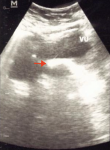

Diagnostic assessment: examination with urologic ultrasonography (USG) showed a hyperechoic structure in the bladder with sizes of 175 mm x 125 mm (Figure 1). The size of the left kidney was normal, but dilatation of PCS was detected at the right kidney without stone formation. A photograph of the kidney, ureter, and bladder (KUB) showed a radiopaque image at the pelvic cavity with a size of 45x30 mm and an image of the double-J stent in the right thoracic paravertebral space (Figure 2). A urological computed tomography (CT) scan showed stone density in her bladder with a size of 48x 21x23 mm and the inserted stent in the right ureter (Figure 3). Her blood components were in normal limits.

Figure 1: urologic ultrasonography showed a hyperechoic image in the bladder with sizes of 175 mm x 125 mm (red arrow)